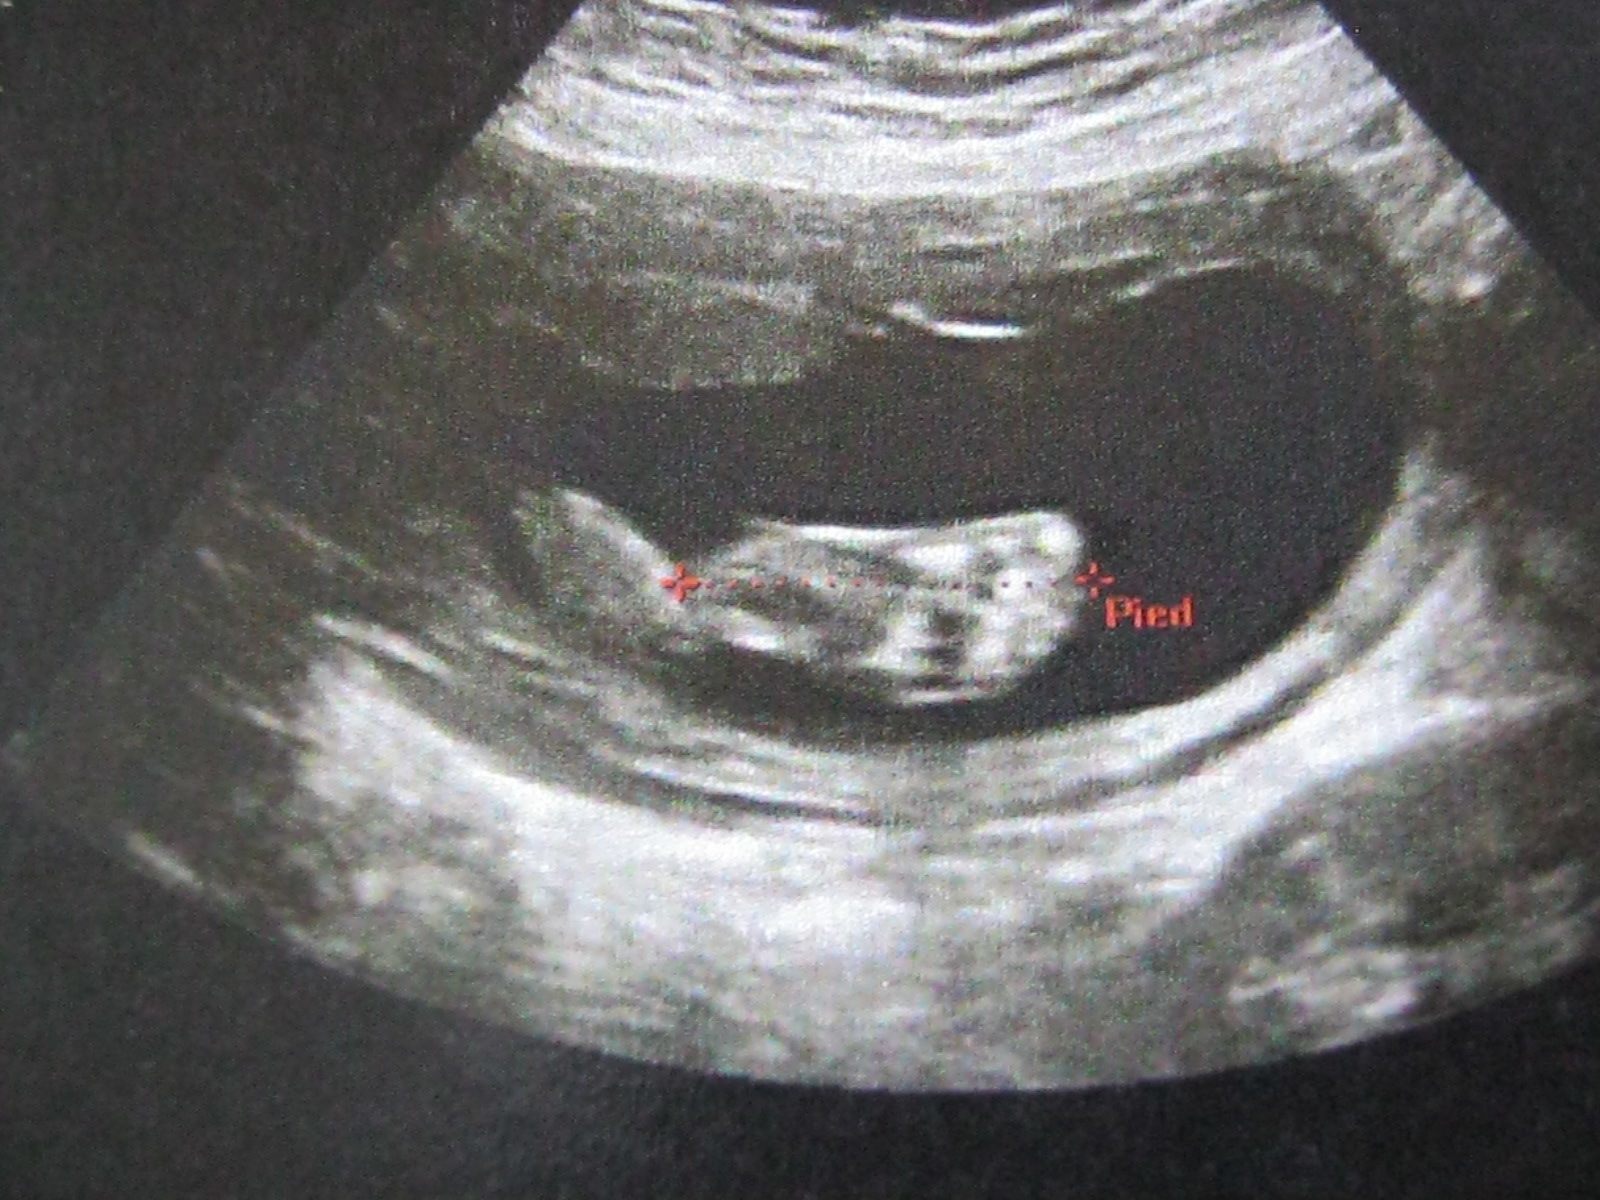

Alors petit résumer petit crapaud fait 430gr tête a gauche et cucu a droit bouge bien, tout les organes sont très bien et le coeur au top du top, pour moi coté poids toujours rien a signaler.

• IMG_0133.JPG

IMG_0133.JPG

245.4 KB · Affichages: 140